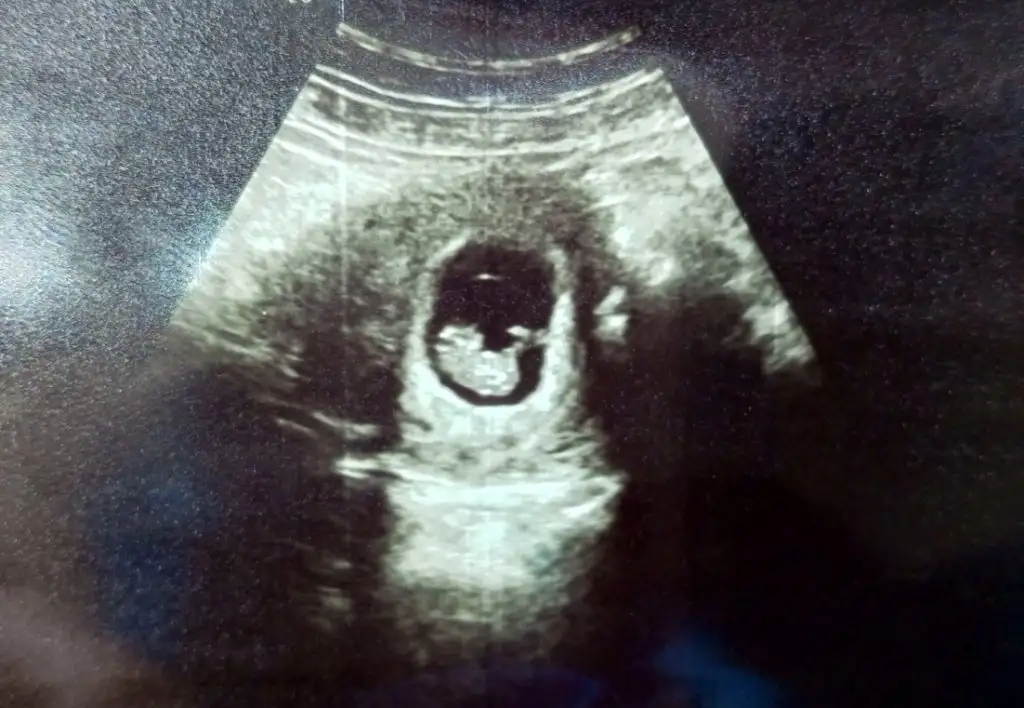

Oyy minnoş yaaMeyaba teyseleyim bu gruptan annem hamile çıktı şimdi 8 haftalık bir minik oldukRabbim isteyen herkese en güzel zamanda nasip etsin

Sorma hergün nasıl zaman geçicek diyorum ama aslında çok da hızlı geçiyorOyy minnoş yaazaman çabuk geçiyor ne ara 8 oldu maşallahh

İnşallah inşallah canım amiinnSorma hergün nasıl zaman geçicek diyorum ama aslında çok da hızlı geçiyorİnşallah rabbim hepinize nasip eder de kardeşleri çoğalır

Teyzesi yesin onuuu maşallah kuzumMeyaba teyseleyim bu gruptan annem hamile çıktı şimdi 8 haftalık bir minik oldukRabbim isteyen herkese en güzel zamanda nasip etsin

Oy maşallahMeyaba teyseleyim bu gruptan annem hamile çıktı şimdi 8 haftalık bir minik oldukRabbim isteyen herkese en güzel zamanda nasip etsin